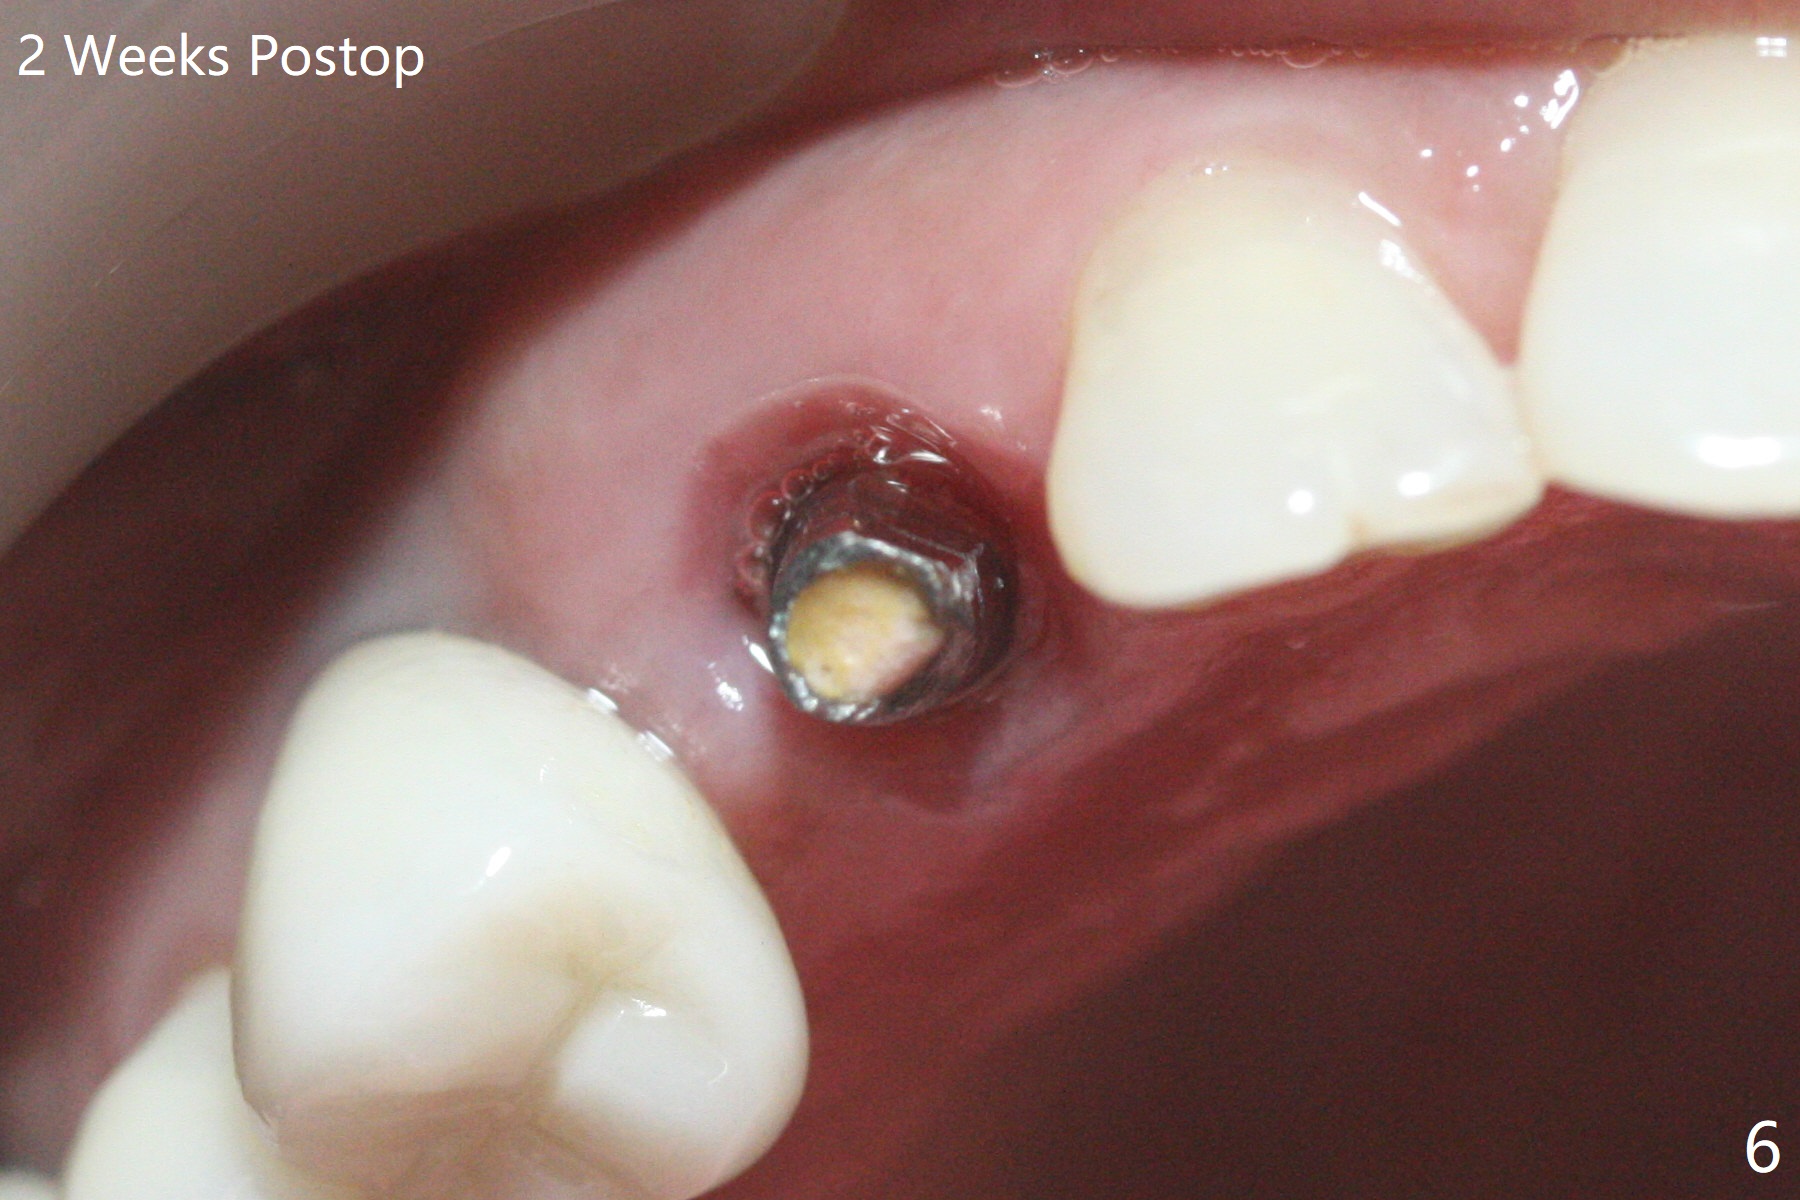

When the recemented crown at #6 is removed, the post is found to have been fractured. When the tooth is extracted, the socket walls are found intact. After moving the initial osteotomy (Fig.1) mesial, a 3.8x13 mm implant is placed (Fig.2). Clinically it appears supracrestal lingually. So the implant is placed deeper, but a cemented abutment is incompletely seated (Fig.3 <). When a longer abutment is used (easy grasping), it is seated completely (Fig.4). Then sticky bone is packed (Fig.5 *). When an immediate provisional is fabricated and seated, PRF membranes are inserted into the remaining gap between the gingiva and the provisional. Free hand surgery takes time and more intraop X-ray. It is inconvenient with nervous patients. The socket heals 2 weeks postop (Fig.6). The provisional will be next relined and reseated. It is difficult to insert gingival retraction cord 3.5 months postop because of the deep mesial margin. When an abutment with longer cuff is placed, the packing is easier (no biologic width violation, Fig.7 (^: resorbed mesial crest), as compared to Fig.5). When the crown is cemented (un-esthetic due to failure of use of temporary abutment), the metal shows at #5 with gingival recession because of buccal placement (Fig.8-10). Bone resorption is severe between #5 and 6 (Fig.7), as related to large gingival embrasure (Fig.9 *). When #5 crow is redone, move the gingival margin apical and fabricate provisional.